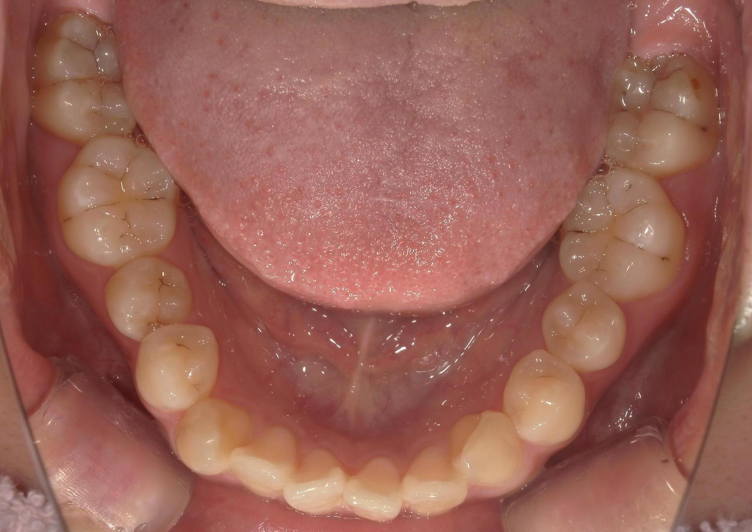

BEFORE